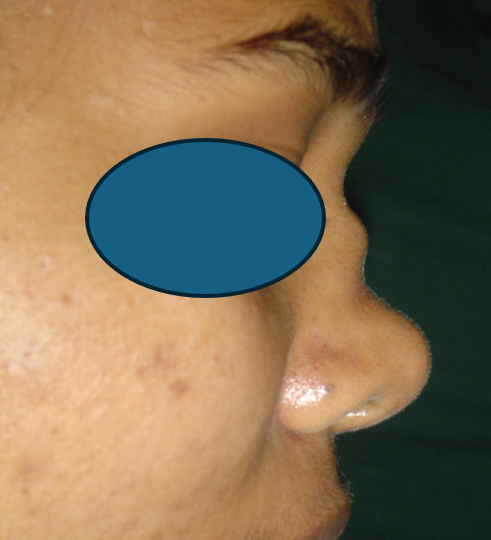

RHINOPLASTY

Cosmetic